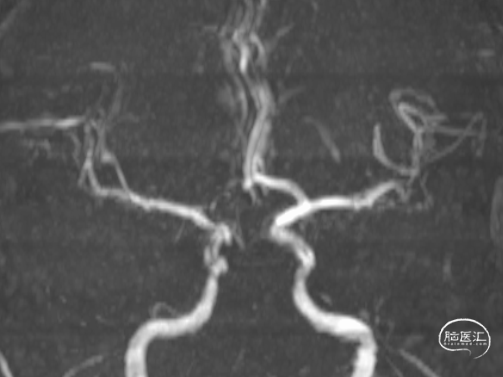

5.双侧椎-基底动脉、双侧大脑后动脉、右侧大脑前动脉闭塞;

6.右侧颈内动脉狭窄;

7.脑动脉硬化。

MRA